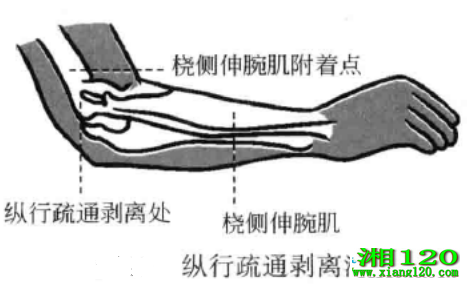

1、纵行疏通剥离法

当粘连服痕病变发生在肌腱、韧带附着点时,将刀口线沿肌纤维、韧带走向平行刺入患处,当刀口接触到骨面时,按刀口线方向疏剥,并按照粘连和瘢痕的面积大小,分几条线进行疏剥,不可横行剥离。